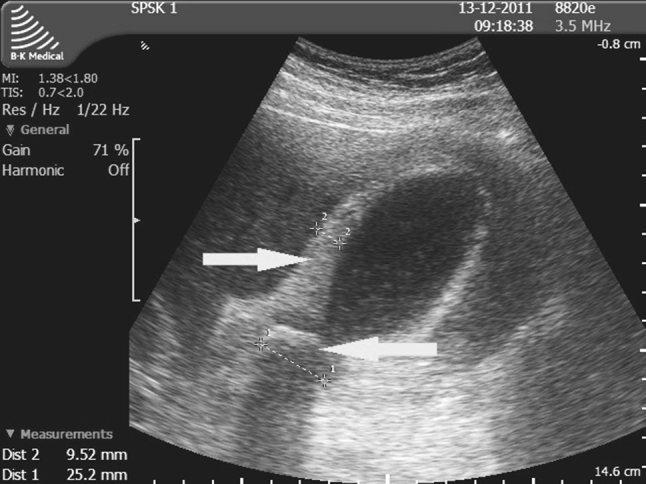

Q.46. A patient was diagnosed with obstructive jaundice. What is the best method to diagnose common bile duct obstruction?

Correct Answer : A

The best method to diagnose common bile duct obstruction is ERCP. It allows direct visualization of the bile duct and pancreas and can also be used to treat obstruction, such as removing stones.